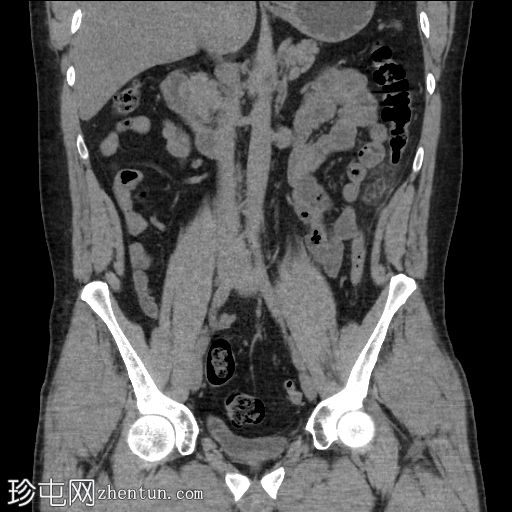

冠状位

平扫

左下腹降结肠旁可见卵圆形脂肪密度影,边缘密度略高,邻近脂肪组织呈条索状改变(冠状位和矢状位)。

未见肾结石或输尿管结石。

未见腹腔内游离气体或液体。